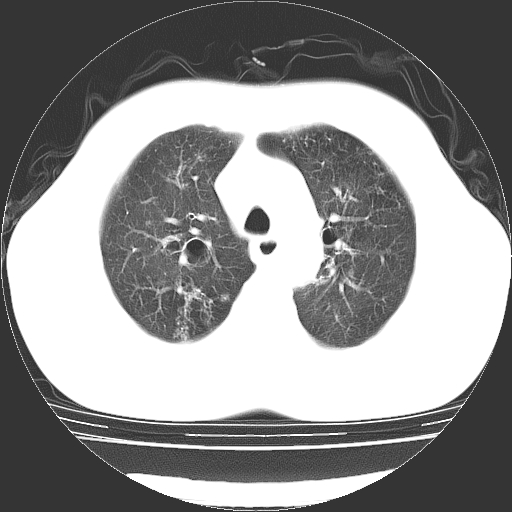

以下是引用zyx168在2006-12-4 15:30:00的发言:[br]经典!支气管肺囊肿并感染。

以下是引用dyqct在2006-12-4 17:11:00的发言:[br]典型的囊状支扩合并感染。

以下是引用liaoqiang在2006-12-4 16:12:00的发言:[br]局部肺叶内可见扩张的支气管壁,考虑为支扩。部份囊样影内有小液平和肺内散布斑片征影、小结节及纤维灶,提示支扩伴感染,且由于局部呈现有树芽征感染以结核可能性大。

以下是引用zhoucan076在2006-12-4 16:48:00的发言:[br]囊状支扩合并感染